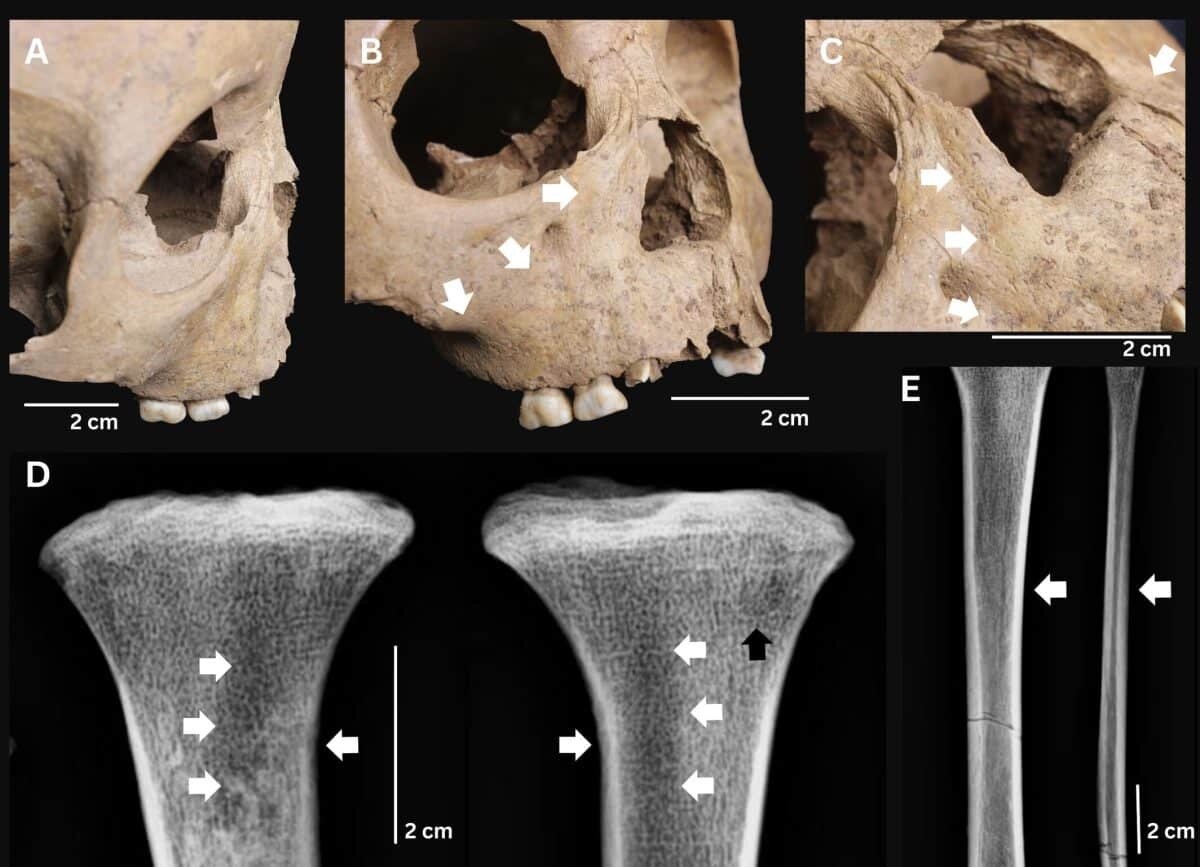

Скелетные изменения, характерные для врожденного трепонематоза: седловидный нос с костным разрастанием, поражение верхней челюсти, а также специфические остеолитические изменения большеберцовой кости на одном из исследованных скелетов / ©The International Journal of Osteoarchaeology

Археологи идентифицировали трех несовершеннолетних с комплексом признаков, соответствующих врожденному трепонематозу. Два случая происходят из памятника Ман-Бак на севере Вьетнама (4000-3500 лет назад), один — из памятника Ан-Сон на юге страны (3800-3200 лет назад). Наиболее показательным оказался ребенок из Ман-Бака в возрасте около 18 месяцев, у которого зафиксировали лунообразные моляры как на постоянных, так и на молочных зубах, множественные поражения костей, утолщение лобной кости и характерные узлы новообразованной костной ткани на длинных костях конечностей. Все это указало на врожденную форму.